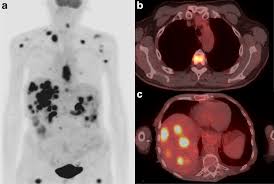

최첨단 현대의학으로 가장 적절한 방법이 양전자단층촬영술(Positron Emission Tomography, PET)이라고 나는 생각한다. PET는 체내 대사 변화를 촬영하는 기기로 CT나 MRI 다음에 개발된 영상장비이라고 한다.

요즘은 여기에 CT를 붙여서 PET 영상과 CT 영상을 융합해 서로 약점을 보완해 검사의 질을 더욱 높이고 있다고 한다.

여기에 방사성 핵종 F-18를 붙여(F-18 FDG라고 함) 혈관 주사하면 빨리 자리는 암세포는 포도당이 더 필요해 정상 세포보다 10∼100배 더 많이 모여들고 이를 방사능으로 촬영해 찾아낸다. 암이 1㎝만 돼도 10조개의 암세포가 있어 CT, MRI 소견이 애매한 경우 유용하게 쓰인다.

PET의 또 다른 장점으로 거의 모든 종류의 암을 찾아낼 수 있다는 것이라고 한다. 일반적으로 암세포는 포도당 대사가 높기 때문이라고 한다.

또 머리끝에서 발끝까지 촬영해 어느 곳에 있는 암이라도 잡아낸다. 다시 말하면 사각지대가 없다고나 할까? 이미 일본에서는 이 방법으로 암을 검진하는 프로젝트를 성황리에 진행하고 있다고 한다.